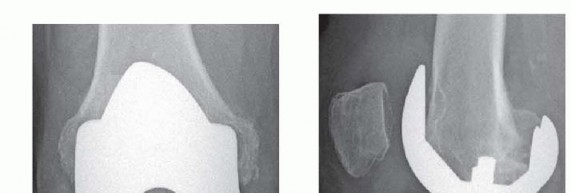

444 Structural Allografting FIGURE 1 FIGURE 2 Indications Bone deficiency, a common theme in revision total k…